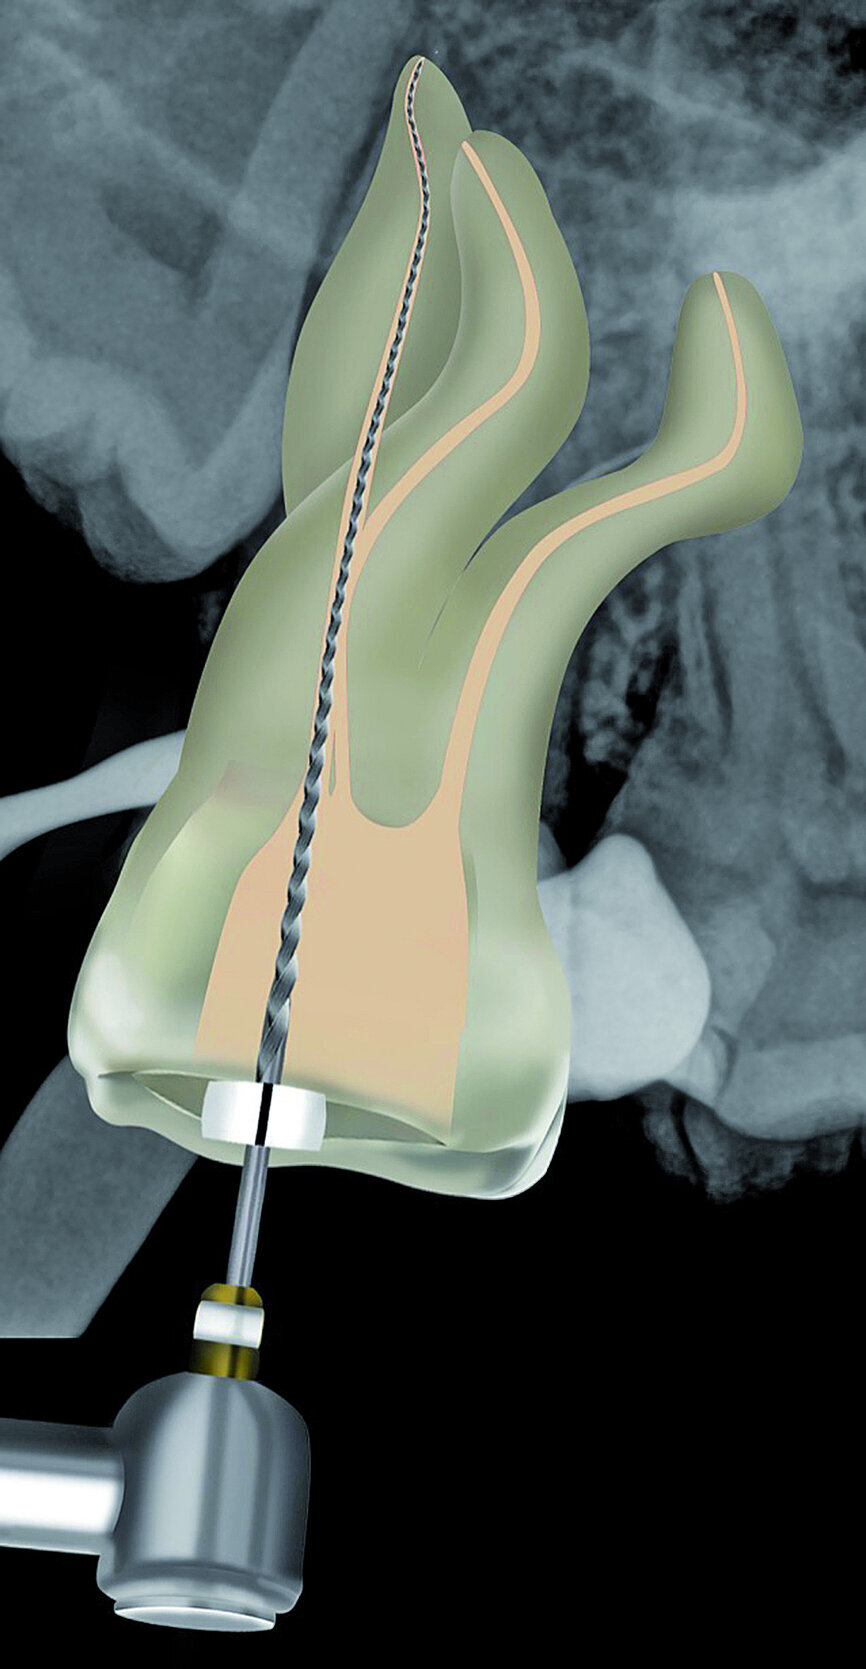

Fig. 21: A size 08 K-File in the M4 reciprocating handpiece was used to initiate the preparation of a reproducible micro glide path.

The pulp chamber was filled with Glyde (Dentsply Sirona) before the canals were carefully negotiated to full working using pre-curved size 08 K-Files (Fig. 19). Working length measurements obtained from an electronic apex locator reading corresponded with the lengths obtained from the 3D Endo Software. These measurements were also confirmed radiographically (Fig. 20). A reproducible glide path was prepared in each root canal system with the size 08 K-File in an M4 Reciprocating handpiece (Sybron Endo; Fig. 21), followed by making a size 10 K-File ‘super loose’ (Fig. 22). A ProGlider (Dentsply Sirona) was used in a rotary motion to expand the glide path in the palatal root canal (Fig. 23). Considering the sharp and severe curvatures in the two buccal canals, it was decided to convert the ProGlider instrument into a manual file to expand the glide path in these tortuous canals with more safety (Fig. 24). The manually adapted ProGlider was used in a balanced force motion up to working length. In addition, to create more safety during the canal preparation of the two challenging buccal root canals, it was also decided to use the reciprocating WaveOne Gold Glider (Dentsply Sirona; Fig. 25), after the ProGlider instrument to further expand the glide paths. The WaveOne Gold Glider was used in 4–8 backstroke brushing motions from working length, in the two buccal root canal systems.